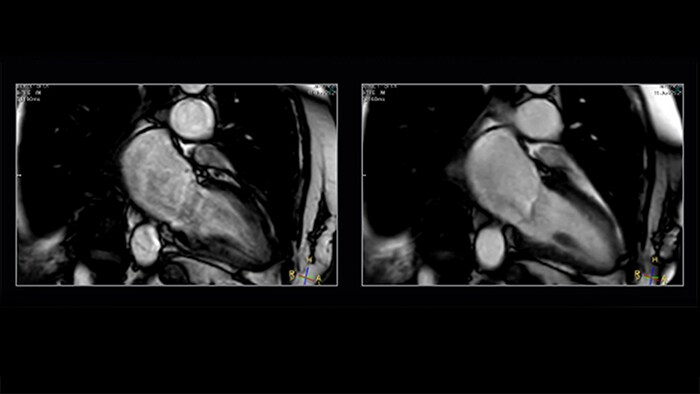

Shorter-breath holds are particularly impactful for patients who cannot manage the length of the breath-hold instruction. Mr. Strachan commented, “using Compressed SENSE sometimes pulls a non-diagnostic study into being a diagnostic study. That itself is very valuable.” For example, see Fig. 1

Figure 1. Shortening acquisition and denoising from C-SENSE provides confidence in long-axis cine of a patient with atrial fibrillation. Left to right: SENSE x2, C-SENSE x4.

The impact of motion is reduced by Compressed SENSE in two ways. As well as allowing data to be acquired in a shorter duration* (so less movement* has occurred during readout), it also intrinsically includes denoising, which is a feature of any compressed sensing based acceleration method. If a motion artifact has a similar appearance to the smeared-aliasing which is deliberately produced by the incoherent under sampling which Compressed SENSE employs, the reconstruction may filter some of it out.